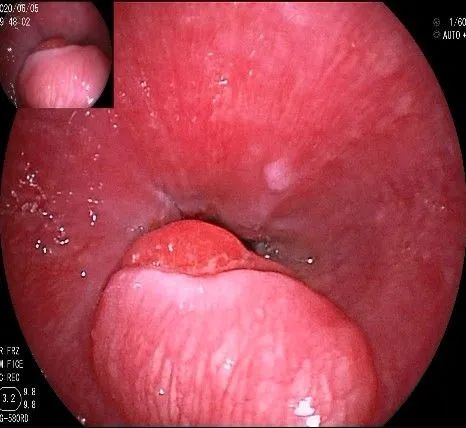

我们的思路:病变长径约2.0cm,位置活动,倒镜后先在胃底侧粘膜下注射,使病变向食管腔方向抬举,然后再在食管腔内做粘膜下注射切开,以获得一个好的术野,果然,注射后粘膜抬举明显,瘤体被挤向口侧。

在食管腔内,瘤体的两侧行粘膜下注射后,在瘤体顶部纵向自口侧向肛侧切开食管粘膜。

向下一直切开至齿状线处,白色为鳞状上皮,红色为腺上皮,颗粒样的部分,就是炎性息肉。切开后可见瘤体为白色,表面有血管网,质地较韧。